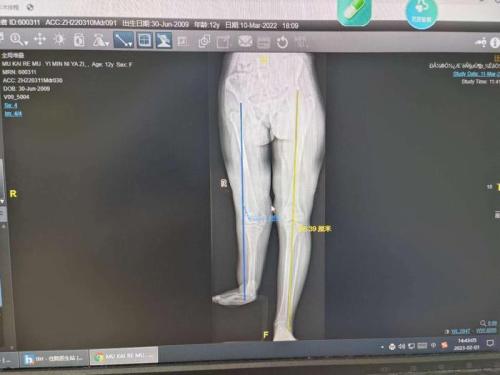

敏敏术前的医学影像显示,其双腿长度相差十几厘米。

马磊告诉记者,敏敏两腿长度相差十几厘米,因此走路的时候臀部朝一侧歪,而正值生长发育高峰期的她,如今腰椎也出现了倾斜,急需手术治疗。“她和我女儿差不多大,这让我更加心疼这个小女孩。”